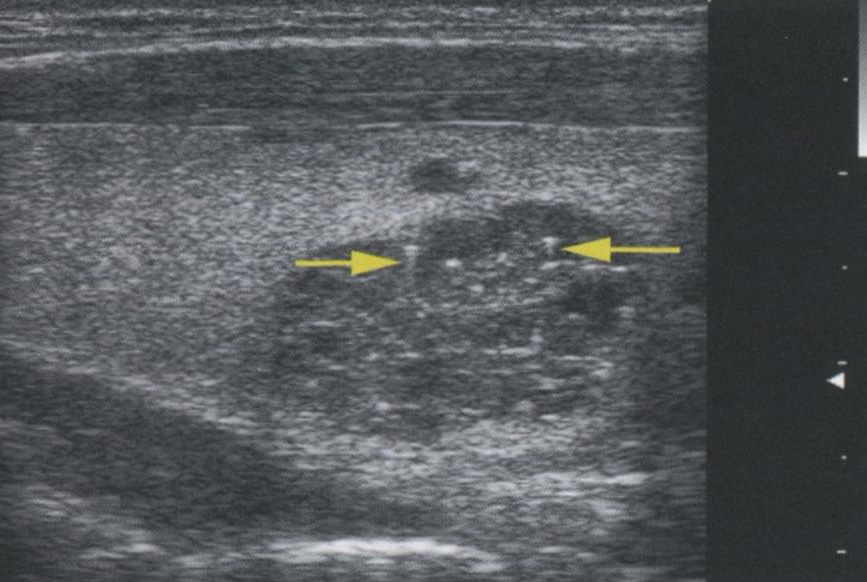

Однако усиление сигнала происходит не только при наличии кистозных узлов. Любая структура, вызывающая минимальное затухание УЗ-сигнала, будет иметь усиление кзади от себя. На рис. 2.13 продемонстрировано усиление сигнала кзади от солидной аденомы ПЩЖ. На рис. 2.14 показано усиление сигнала позади доброкачественного коллоидного узла. Из-за высокого содержания жидкости и коллоида в узле и, как следствие, уменьшения клеточного компонента затухание сигнала в этом образовании происходит в меньшей степени, чем в окружающей ткани щитовидной железы.

Рис. 2.14. Усиление сигнала. Этот доброкачественный коллоидный узел содержит много жидкости и коллоида, что приводит к уменьшению клеточного компонента. Сниженное затухание сигнала в узле обусловливает усиление сигнала, несмотря на то что этот узел является солидным